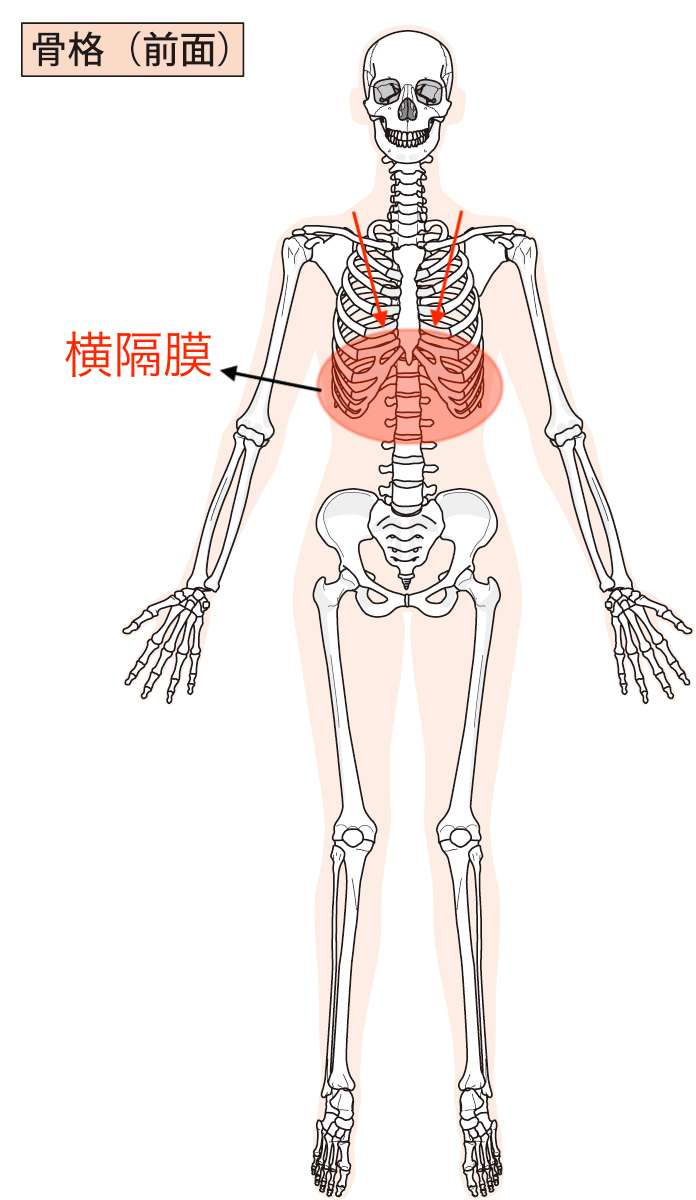

動きをチェックしてから全身の状態を検査していくと、胸椎(背骨)の歪みと横隔膜の硬さがありました。

二枚目の画像では、肋骨の中に筋肉質のものが確認できると思いますが、それが「横隔膜」です。

横隔膜は過緊張を起こしていて、深呼吸を確認すると深く息が吸えていないことが確認できました。

ご相談いただいた方の場合、この横隔膜が過緊張を起こしており、その影響で上記の画像のように肩が横隔膜の方向へ引っ張られるような力がかかっていました。

また、先ほどお伝えした胸椎(背骨)の部分にこの横隔膜がくっついているので、その影響もあって胸椎が歪んでいたことがわかりました。

横隔膜の過緊張の影響により、肩こりが慢性的に起こることで首の筋肉も同時に緊張を起こしてきます。

そうすると、頭へ向かう血流にも影響を与えるために、頭痛が発生しているということが考えられました。

ご相談いただいた方の場合は、胸椎の部分と横隔膜に特に問題があったので、自宅でできるセルフケアとして「胸椎(背骨」と「横隔膜(溝落ち)」を温めることからはじめていただくようにお伝えさせていただきました。

今回ご相談いただいた方の場合だと肩こりだから「肩」というわけではなくて、「胸椎」と「横隔膜」だったわけです。